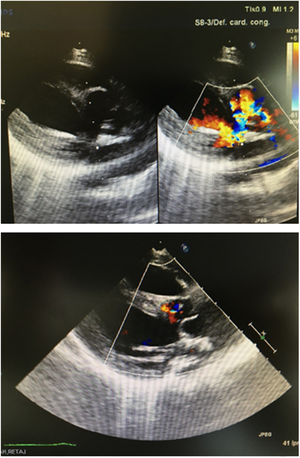

El primer paciente, mujer, presentaba un truncus arteriosus con válvula truncal tetracúspide y displásica. Con 5 días de vida, fue intervenido realizándose cierre de comunicación interventricular más conducto avalvulado de 8mm en el lado derecho y tricuspidización valvular más adelgazamiento de velos. Progresivamente fue desarrollando insuficiencia de su válvula truncal hasta hacerse severa y se reintervino con 14 meses. Descartado el procedimiento de Ross y una prótesis, las opciones de reparación resultaban escasas8. El anillo valvular medía 17-18mm de diámetro y el cilindro se confeccionó con un rectángulo de 18×80mm. Una vez implantada la neoválvula7, el conducto previo fue recambiado por uno valvulado del n.o 18. El resultado inicial y a los 6 meses fue satisfactorio (fig. 3), con una regurgitación central trivial sin gradiente. Empíricamente, se mantuvo antiagregado. Tres años más tarde, presenta una insuficiencia moderada por inmovilidad de uno de los velos.

Paciente 2Nuestro segundo caso se trataba de una niña con ventrículo único, discordancia ventriculoarterial, comunicación interventricular, hipoplasia de arco aórtico y estenosis subaórtica. En periodo neonatal se realizó un switch paliativo9 más cerclaje de tronco neopulmonar, con buen resultado. Una dilatación progresiva del anillo neoaórtico produjo una regurgitación valvular hasta convertirse en moderada-severa, a pesar de velos normales. La alternativa de una cirugía tipo David o Yacoub fue descartada, por el pequeño tamaño. Con 6 meses fue reintervenida, desmontando el cerclaje y Lecompte previos para acceder a la neorraíz aórtica10. El diámetro era de 15mm y las dimensiones del rectángulo para la confección del cilindro de 15×67mm. El resultado inmediato fue satisfactorio, con regurgitación central trivial (fig. 4). Lamentablemente, falleció 6 meses después por una sepsis de origen respiratorio, en espera del segundo tiempo para la reparación univentricular.

Paciente 3Finalmente, el tercer caso, un niño, nació con una atresia valvular aórtica, hipoplasia de aorta y arco, además de válvula pulmonar displásica (gradiente 60mmHg). Se daba la circunstancia de que dicha válvula pulmonar actuaba como sistémica, dando flujo anterógrado a la aorta descendente y retrógrado a los troncos supraaórticos y las coronarias. Con 13 días y 3,1kg fue intervenido, realizándose un procedimiento híbrido: cerclaje de ambas ramas pulmonares más implantación de stent ductal, además de neoválvula en posición pulmonar. Para ello, la arteria pulmonar fue seccionada inmediatamente por debajo de la bifurcación. Una de las comisuras fue abierta longitudinalmente hasta el triángulo subcomisural, dadas sus dimensiones reducidas (11mm). El cilindro se realizó a partir de un rectángulo con medidas de 11×50mm. La ecografía inicial mostraba una insuficiencia ligera paracomisural, coincidente con la apertura longitudinal previa (fig. 5). Habiendo descartado la opción de una reparación biventricular compleja (Norwood-Rastelli o técnica de Yasui) que dejase nuestra neoválvula en posición sistémica, fue trasplantado 2 meses después. Un año más tarde, se encuentra en buen estado.